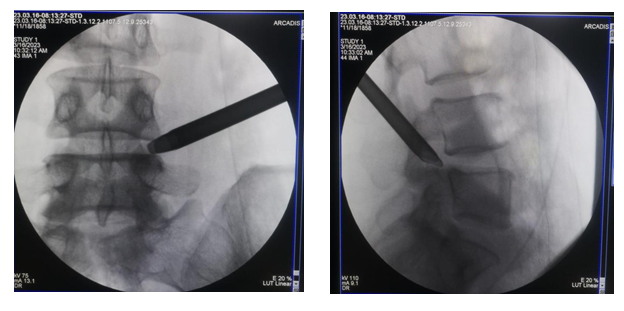

与患者及家属充分沟通后建议行椎间孔镜微创手术治疗,在局麻强化下行「全可视下椎间孔镜腰椎间盘突出髓核摘除术」治疗。术后即可基本恢复正常行走。

经皮小切口内镜下椎间盘切除术始于 20 世纪末,是一种微创手术,痛苦小,失血少,住院时间短,可以在局部麻醉下进行的手术。

椎间孔镜技术是一种内镜技术,它里面有一个「镜」,一个「椎间孔」,就是把内镜通过椎间孔的天然腔隙,放到我们出现问题的椎间盘位置,并对已有的椎间盘突出、疝出或者游离,在无损伤的或者最低限度损伤的情况之下,进行髓核的摘除。

借助天然的椎间孔位置,可以最大程度地避免神经的牵拉,避免前方血管的损伤与后方骨骼、肌肉系统过多的切除,达到对椎间盘突出、疝出的地方进行减压。